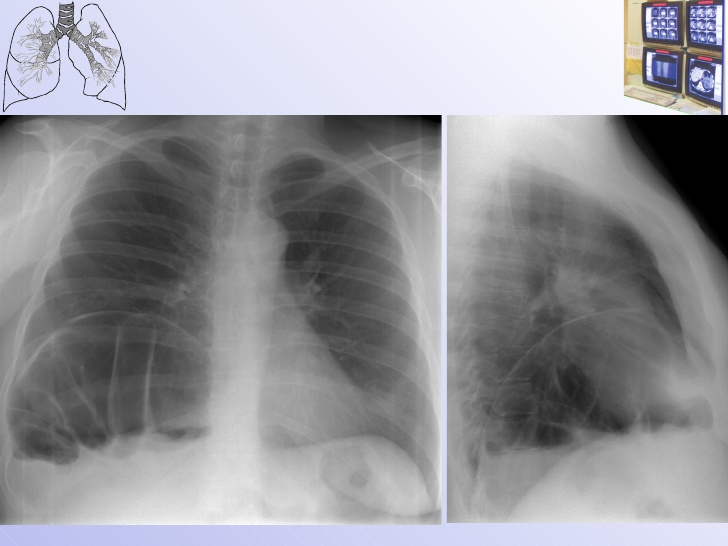

Рентгеновские снимки опухоли Панкоста